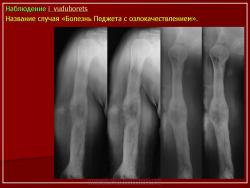

Вторичная остеосаркома может развиваться на фоне болезни Педжета, остеобластомы, множественных врожденных экзостозов. В работе выделено 3 остеосаркомы на фоне болезни Педжета, 3 - постлучевых остеосарком и 1 - остеосаркома костей таза при болезни Оллье.

Макроскопическая картина выявляет границу саркоматозного компонента, особенно если разрушена кортикальная пластинка пораженной кости.

Микроскопическая картина остеосаркомы при болезни Педжета - удается выявить мозаичные структуры цементирования в окружении веретеноклеточного саркоматозного компонента, гистологический вариант остеосаркомы и степень дифференцировки опухоли отличается от случая к случаю. В наших наблюдениях все три остеосаркомы обладали признаками низкой степени дифференцировки с фокусами патологического остеоида.

I стадия (литическя) — острая стадия, определяется деструкция кортикального слоя в виде очагов пламени или в форме клина.

II стадия (переходная) – смешанное поражение (остеолиз + склероз).

III стадия (склеротическая) – преобладание склероза с возможной деформацией кости